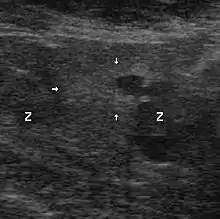

L'orientation diagnostique repose sur deux éléments clés : le dosage sanguin du PSA suivi d'un toucher rectal. L'anormalité de l'un ou de ces deux éléments laisse soupçonner un cancer de la prostate. Il sera confirmé ou infirmé par l'analyse sous microscope d'échantillons de la prostate (biopsies prostatiques transrectales échoguidées).

Histologie

Le diagnostic est obtenu par des biopsies prostatiques multiples, réalisées de manière échoguidée et par voie transrectale. Elle permet également de réaliser le score de Gleason, de grande valeur pronostique.

L'examen clinique fondamental est le toucher rectal. L'élastographie ultrasonore (échographie évoluée) est une technique complémentaire qui peut être préconisée autant en raison du faible coût de l'examen, de son absence d'effet secondaire et de sa sensibilité, dès que le taux d'antigène prostatique spécifique est hors norme[47],[48].

Échographie avec biopsies transrectales

Il n'existe actuellement aucun examen d'imagerie de pratique courante susceptible de détecter seul un foyer d'adénocarcinome prostatique avec une sensibilité et une spécificité satisfaisantes.

Contrairement à une idée encore largement répandue, et bien que cet examen soit ainsi encore souvent prescrit, l'échographie endorectale, seule, n'a pas d'utilité pour le diagnostic positif du cancer de la prostate, au regard du désagrément qu'elle est susceptible d'occasionner. Elle prend, en revanche, tout son intérêt lorsqu'elle sert à guider des biopsies prostatiques. Les autres modalités d'imagerie (scanner, IRM) ont un intérêt dans le bilan d'extension.

Technique

Une sonde d'échographie endorectale munie d'un guide d'aiguille est introduite dans le rectum. Les biopsies sont effectuées avec des aiguilles munies d'un mandrin encoché. Le mandrin pénètre le premier. L'aiguille vient le recouvrir, pour trancher et emprisonner ainsi le fragment de prostate situé dans l'encoche. Les mouvements du mandrin et de l'aiguille sont automatisés par un système de ressorts et le prélèvement est effectué en quelques centièmes de seconde. L'écran de l'échographe, muni d'un repère représentant le trajet de l'aiguille, permet, ainsi, des tirs biopsiques très précis.

Le nombre des biopsies, et l’endroit où elles doivent se faire, ne sont pas bien codifiés et de nombreux protocoles ont été proposés : le but est d'obtenir un échantillonnage aussi représentatif que possible. Actuellement, il est fréquemment réalisé 5 à 6 prélèvements par lobe, soit 10 à 12 au total. Ces nombres peuvent être diminués ou augmentés en fonction de la taille de la prostate, de la tolérance du patient, ou bien s'il s'agit d'une deuxième série de biopsies.